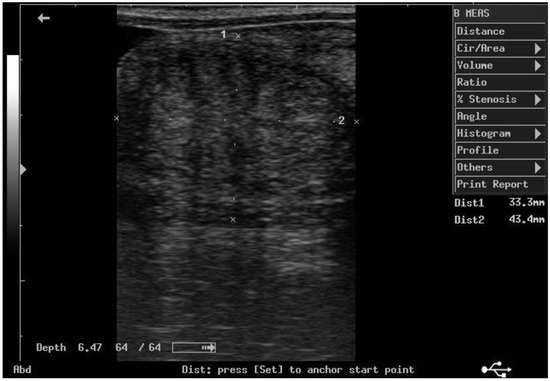

According to ultrasonographic records (Table 1), the mean T diameters did not differ significantly between PPH and NPPH at any time, whereas the mean M diameter of the PPH was larger than the NPPH only until PP Day 7 (Figure 1, Figure 2, Figure 3 and Figure 4). The Bonferroni post hoc test confirmed the ultrasonographic data obtained by ANOVA for repeated measures, when PPH and NPPH were considered across time. Moreover, when only time was assessed, the Bonferroni post hoc test highlighted similar significant changes occurring between PP Days 1–3 and 14–28 (p-value ranging between <0.05 and <0.001) and between PP Days 7 and 14–28 (p-value ranging between <0.05 and <0.01) for the M and CCJ. In relation to T, significant changes were detected among all the times of observation, with p-value ranging between <0.05 and <0.001.

Figure 1. Ultrasound image of the middle tract of the post-pregnant uterine horn, at day 7 postpartum.

The diameter of the CCJ in the PPH was not measurable until PP Day 3, then the mean diameter of the CCJ resulted larger in the PPH in comparison to NPPH only at PP Day 7. The first PP ovulation, detected by ultrasonography, occurred 11.9 ± 1.3 days after foaling. At the first PP ovulation, the follicle diameter was 45.1 ± 2.8 mm.